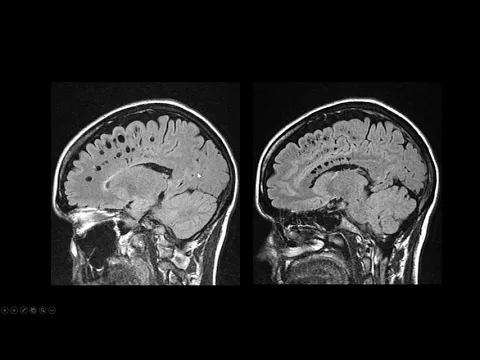

Según la Scientific American, que analizó los resultados de un estudio de resonancia magnética con alpinistas que intentaron el Everest, solo uno de los trece participantes volvió con una imagen cerebral considerada normal. Los otros doce presentaron atrofia cortical o agrandamiento de los espacios de Virchow-Robin, una alteración estructural generalmente asociada al envejecimiento y raramente observada en adultos jóvenes y sanos.

Los resultados de la expedición al Everest fueron particularmente relevantes. De los trece participantes analizados, solo uno presentó una estructura cerebral normal. Los demás mostraron alteraciones como atrofia cortical difusa y ensanchamiento de los espacios perivasculares.

Estas alteraciones indican que daños estructurales pueden ocurrir incluso en ausencia de síntomas perceptibles durante la escalada.

Alteraciones en los espacios de Virchow-Robin indican impacto en la circulación cerebral y en el sistema de drenaje del cerebro

Los espacios de Virchow-Robin son canales microscópicos asociados a los vasos sanguíneos cerebrales y al sistema de drenaje del cerebro.

El ensanchamiento de estas estructuras sugiere alteraciones en la circulación cerebral o en la presión del líquido cerebroespinal, indicando que la exposición a altitudes extremas puede comprometer el equilibrio interno del cerebro.

En individuos jóvenes y sanos, este tipo de alteración es inusual, reforzando el impacto fisiológico de la hipoxia prolongada.